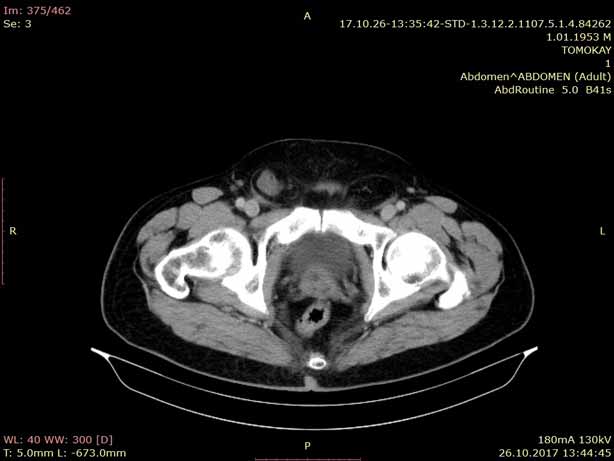

Bilgisayarlı Tomografi (BT) ileri bir X ışını teknolojisidir. BT vücudun istenilen bölgesinden kesit kesit (dilim şeklinde) görüntü alınmasına olanak verir. Bu gelişmiş resimler dönen odaklanmış bir X ışını üreticisinin hastanın etrafında dönmesiyle oluşturulur. Vücudun farklı bölgeleri ve organları incelenir.

BT cihazının masasına yatmanız istenecektir. Bu masa yuvarlak bir boşluğun içine doğru ilerleyecektir. Çekim başlayınca BT makinesinden bazı sesler duyacaksınız. Bu sesler sizi rahatsız etmesin; çünkü bu sesler X ışınları oluşurken ve sizin vücut bölgenizden kesit kesit görüntüler alınırken ortaya çıkan seslerdir. Her kesitte BT makinesi ayrı bir görüntü oluşturur. X ışınlarından alınan bilgiler son teknoloji bilgisayar sayesinde görüntü haline dönüştürülür. Görüntüler dijital ortamda tutulur, Workstation (İş istasyonu) sayesinde merkezimizdeki Radyologların bilgisayarlarına gönderilir. Film olarak veya CD ortamında hastaya verilir.

BT ile torakstaki (akciğer, mediastinum, kalp ve damarlar, göğüs duvarı) kitle lezyonu (tümörler), infeksiyon, inflamasyon gibi hastalıklar teşhis edilmektedir.